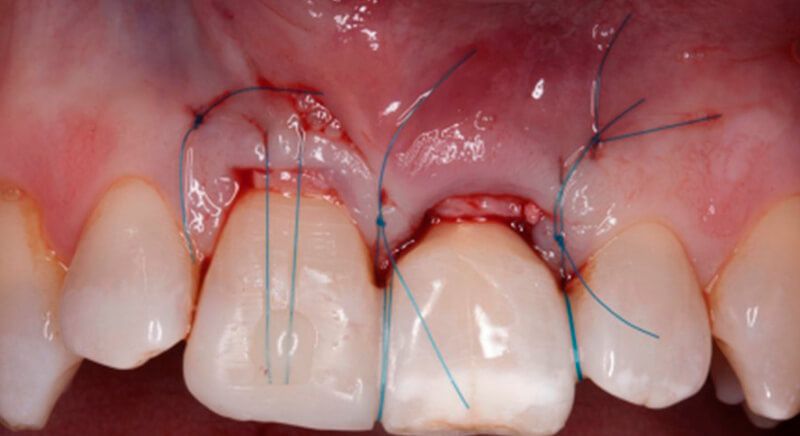

The socket was filled with a xenograft after the extraction and a graft of connective tissue was placed in the vestibular area of the two upper central incisors.

The tissue with epithelium was taken from the palate and de-epithelialized outside of the mouth. This obtains a lamina propria graft with better density and quality than if it were obtained with a single incision to the palate.

Once the hard and soft tissues had healed, 6 months after the surgery, a good volume remained in the vestibular area. It was then that we could consider an implant, using guided surgery to ensure it was placed in the correct three-dimensional position.